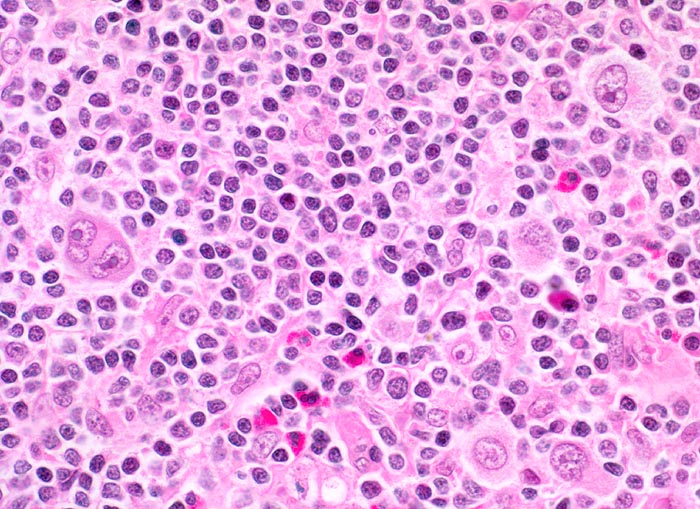

PathoPic – image database / PathoPic ID 3874 - Hodgkin-Lymphom, Mischzelltyp

Hodgkin-Lymphom, Mischzelltyp

Die neoplastischen einkernigen Hodgkin Zellen und mehrkernigen Reed-Sternberg Zellen werden umgeben von einem reaktiven Zellgemisch aus Lymphozyten, Histiozyten, eosinophilen Granulozyten und vereinzelten Plasmazellen.

Reed-Sternberg-Zellen sind grosse mehrkernige Zellen mit spiegelbildlich angeordneten Kernen und grossen eosinophilen Nukleolen. Sie entstehen aus Hodgkin-Zellen. Im Gegensatz zur nodulären Sklerose zeigen die neoplastischen Zellen beim Mischzelltyp keinen Retraktionsartefakt des Zytoplasma.